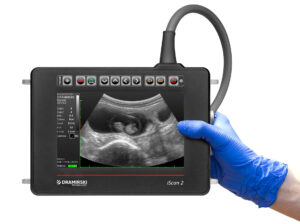

Mobilität und Robustheit

Die Arbeitsbedingungen auf landwirtschaftlichen Betrieben sind alles andere als steril. Das Gerät muss leicht und kompakt sein, um es einfach zwischen Einsatzorten und Betrieben transportieren zu können. Es sollte stoßfest, feuchtigkeits- und staubresistent sowie für niedrige Temperaturen geeignet sein, da Untersuchungen oft in Ställen, in Anbindeständen oder auf tief eingestreuten Flächen durchgeführt werden. Beliebt sind tragbare Geräte, die am Gurt oder Geschirr getragen werden, um die Hände frei zu haben und einfachen Zugriff auf die Benutzeroberfläche während der rektalen Untersuchung zu ermöglichen.

Bildqualität

Obwohl Untersuchungen bei Rindern nicht die gleiche Präzision wie in der Kleintierchirurgie erfordern, ist ein klares und kontrastreiches Bild unerlässlich. Es ermöglicht die Beurteilung der Ovarstrukturen, das Erkennen von Zysten, Follikeln und Gelbkörpern, die präzise Bestimmung des Trächtigkeitsalters, die Diagnose von Pathologien der Gebärmutter, wie Pyometra oder Flüssigkeitsansammlungen, sowie die Kontrolle nach Eingriffen, z. B. Punktion einer Zyste. Wichtige Faktoren sind Auflösung, Sondenfrequenz, Eindringtiefe und die Möglichkeit, Bildparameter in Echtzeit anzupassen.

Art der Sonde

Standard bei der Arbeit mit Rindern ist eine lineare rektale Sonde – lang und schmal, für rektale Untersuchungen geeignet. Sie sollte ergonomisch, widerstandsfähig gegen Beschädigungen und Flüssigkeiten sein. Eine Frequenz von 5–9 MHz bietet einen guten Kompromiss zwischen Auflösung und Eindringtiefe. Fortgeschrittene Geräte ermöglichen auch den Anschluss von konvexen Sonden für Oberflächenuntersuchungen oder Doppler-Sonden zur Beurteilung von Blutfluss.

Bedienkomfort und Zusatzfunktionen

Das Gerät sollte schnell startbar sein, intuitive Moduswechsel wie Tiefen- oder Gain-Einstellungen ermöglichen und Optionen zur Speicherung von Bildern und Videos auf USB, per Bluetooth oder WLAN bieten. Ein Trächtigkeitsmodus mit automatischer Messung von CRL oder BPD erleichtert die schnelle Beurteilung des Embryonalalters. Vorteilhaft ist auch die Integration mit mobilen Apps oder Cloud-Diensten zur Archivierung, Fallbeschreibung und zum Teilen der Ergebnisse mit Landwirten.